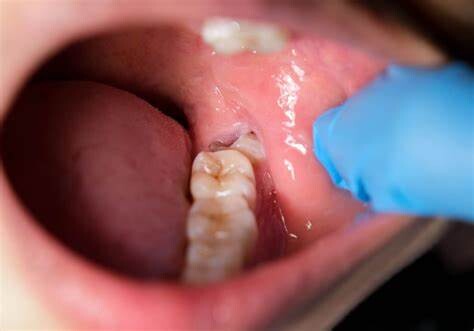

Wisdom teeth promotes Gum Disease

It is a challenging task to clean the area in which the third molars have erupted. Therefore they are at a greater risk of acquiring the periodontal problems. The gum diseases are usually caused by bacteria, and when a tooth can’t be precisely cleaned on a regular basis, the dental plaque gets accumulated around the tooth, which may lead to further complications.

Formation of Cysts or Tumours

If the wisdom teeth problems are not dealt in an appropriate manner, the tooth will develop a sac within the jawbone. This sac has the ability to fill with fluid, which gradually develops into the formation of cyst, damaging the teeth, jawbone, and nerves. There are chances that this cyst could progressively develop into a tumour if untreated which could ultimately result in the removal of tissue and jaw bones.

Mutilates the Neighbouring Teeth

Since there is not enough room for the tooth to grow, it will case the teeth to grow in an abnormal manner. This results in impaction of the teeth, giving rise to many other oral problems. When the wisdom tooth emerges against the second set of molar, it might damage them, increasing the risk of acute infection. It will also have an effect on other teeth, which will intensify the need for an orthodontic treatment to align the other teeth.

Tooth Decay

The fully impacted or the partially impacted wisdom teeth are at greater risk of tooth decay, than other teeth. This usually happens, because of the location of the wisdom tooth, especially towards the back of the mouth, which is hard to clean. Moreover, since it lies at the back of the mouth, there are chances of food getting easily trapped between the gums and the tooth, promoting the growth of bacteria.

You can’t prevent the occurrence of an impacted wisdom tooth, but with a regular dental check-up, your dentist will help you monitor the emergence of the wisdom tooth, with the help of dental X-rays and advanced methodologies, which might indicate the need of wisdom teeth removal.